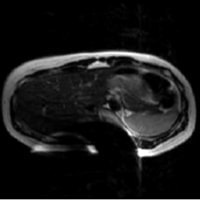

患者様を案内又は搬送する際は、患者様の金属の有無について十分注意をお願いします。金属が体内に入っている方や、 身につけている方は写真上に影響が出ると同時に体内金属が動いたり、発熱したりする場合があり危険な場合があります。 金属があった場合の症例を提示します。

磁気健康器具による影響